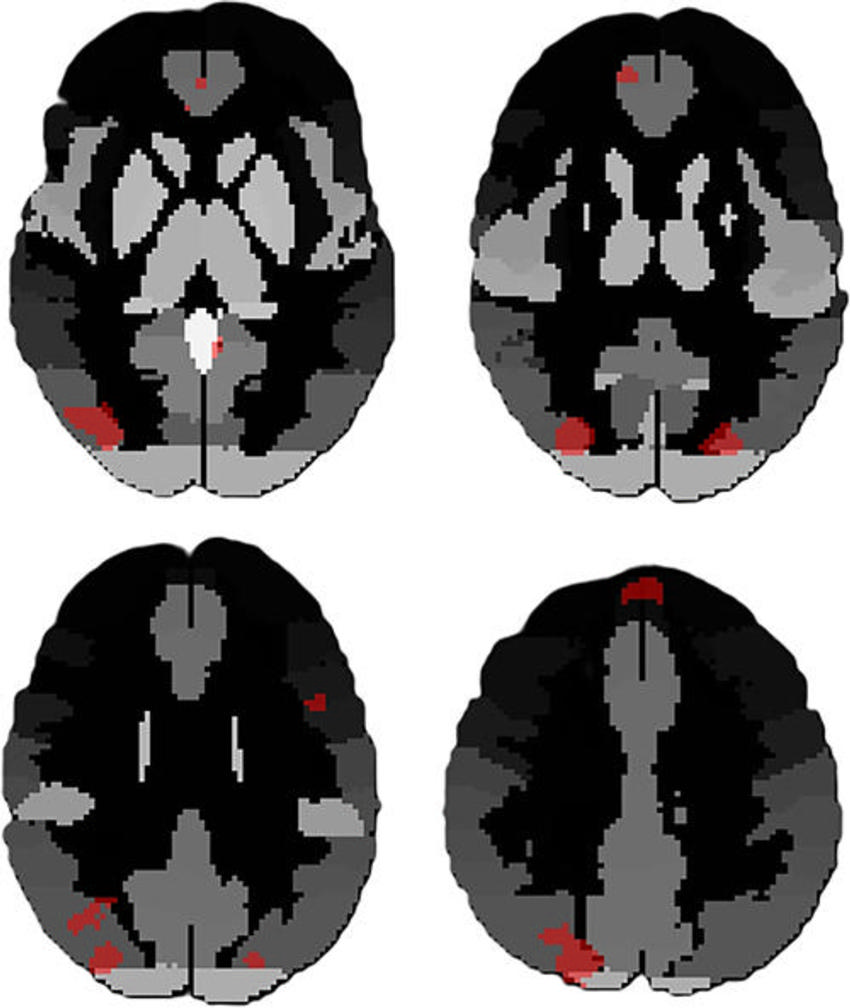

High-res (TIF) version

Figure 2. Upper panel displays functional MRI (fMRI) maps obtained from the functional connectivity multivariate patterns analysis conducted on dataset 1 and dataset 2. In particular, the average connectivity across all participants is illustrated with one of the clusters that showed differences between the groups. The colors depict the r value ranging from red to blue. Images in bottom panel highlight the differences between groups (color coded from red to blue), focusing on the same cluster chosen as a seed in the top row. The average connectivity is illustrated with the contrasted cluster across participants, showing a comparable disparity between the two datasets.